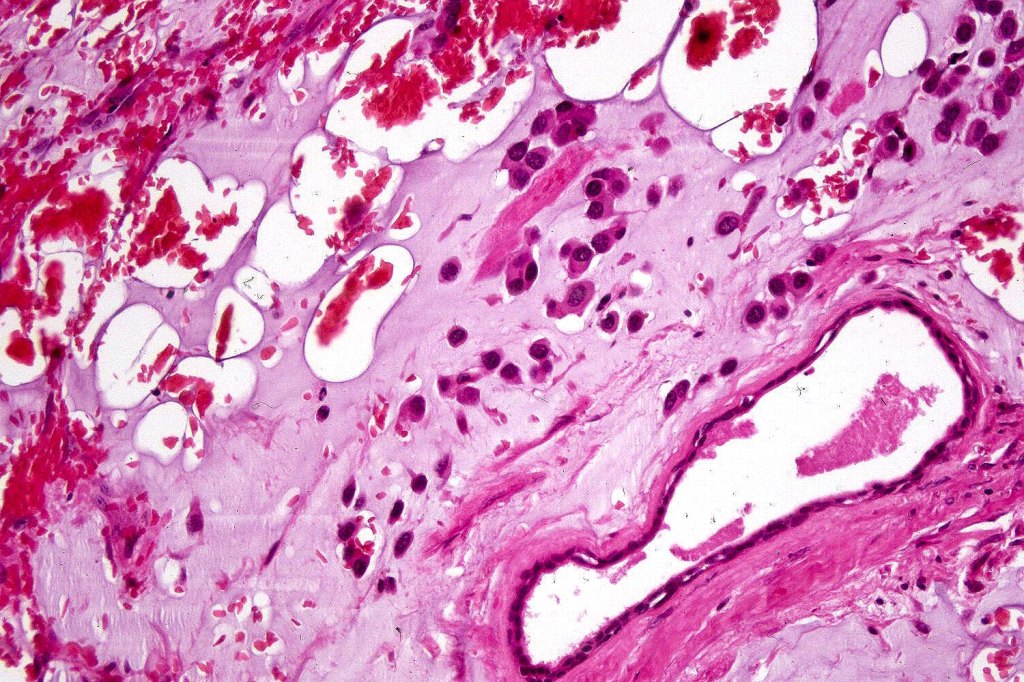

A rare variant of melanoma in which stromal cells produce excess acid mucopolysaccharides inprting a striking myxoid quality. The mucin is Alcian blue & colloidal iron positive, DPAS negative and the melanoma cells stain with typical markeres including S100 & HMB45. It may be seen in primary, recurrent or most often in metastatic lesions. The tumor cells are typically small although occcasionally they are epithelioid. Melanin is often sparse or even avsent making diagnosis difficult. In some examples, a pseudoglandular appearance is seen.

The differential diagnosis is very wide and can include numerous myxoid soft tissue tumors and epthelial mucin-secreting carcinomas. Diagnosis depends on clinical history, mucin stains and the judicious use of immunohistochemistry.